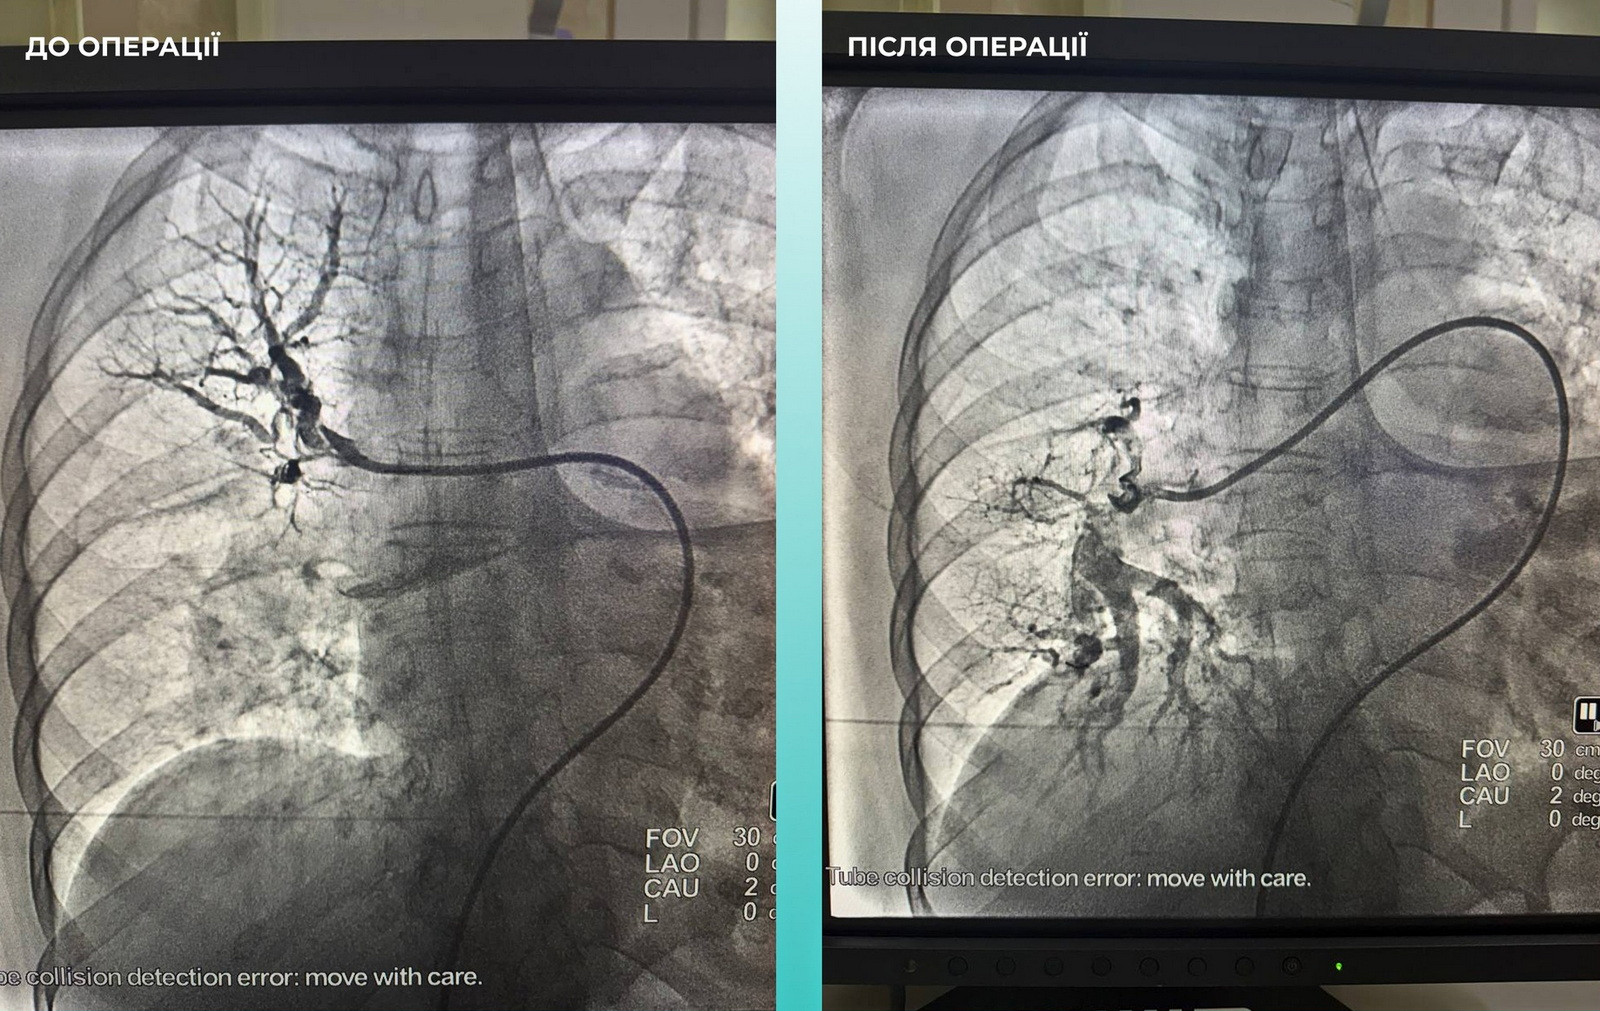

Медики міської клінічної лікарні № 10 успішно провели унікальну операцію – одночасно прооперували гострий мозковий інсульт і тромбоемболію легеневої артерії.

Одеситка потрапила до лікарні з важким гострим мозковим інсультом. Під час обстеження на комп’ютерному томографі лікарі виявили закриття середньої мозкової артерії.

Також медики звернули увагу, що пацієнтці важко дихати, тож додатково обстежили легені. Діагноз ускладнився ще й тромбоемболією легеневої артерії.

Мультидисциплінарна команда лікарів ухвалила складне, але життєво необхідне рішення — провести одночасну тромбектомію з мозкової та легеневої артерій.

Операція пройшла успішно. Наразі пацієнтка почувається значно краще: вона при свідомості та вже рухає кінцівками.